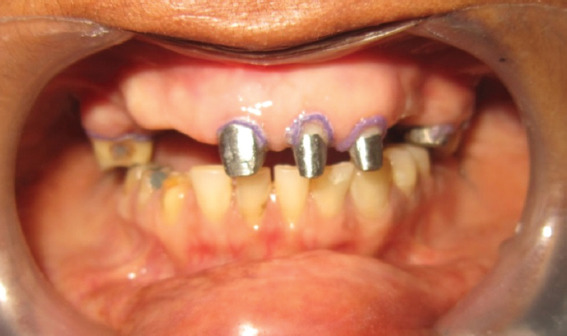

Case presentation: A 41-year-old female presented with a history of difficulty in chewing and poor appearance. Examination revealed that the patient had missing teeth in the maxilla (12, 13, 14, 15, 23, and 24), in the mandible (46 and 47), and in teeth 11, 21, 22, 25, 36, 37, 43, 44, and 45 were root canal treated, of which 21, 22, and 25 did not have any coronal structure and 36 had a discharging sinus. The periodontal condition of the remaining teeth was good and the vertical dimension was reduced. This patient had multiple missing and badly damaged anterior teeth. Hence, Hobo and Takayama twin stage method was used to re-establish the anterior guidance for full mouth rehabilitation.

Conclusion: Worn dentition requires a very careful and calculative approach due to its complex nature. Hobo twin stage technique is based on case studies from which the mathematical values for anterior guidance and posterior disocclusion are determined and thus minimizes the clinical procedure duration and produces good masticatory function.